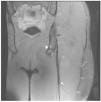

Figura 4 La imatge coronal en T2 amb supressió de greix dels isquiotibials esquerre durant el seguiment postquirúrgic mostra l’ancoratge metàl·lic a la tuberositat isquiàtica (punta de fletxa) i sutures peritendinoses representades per artefactes peritendinosos de susceptibilitat magnètica (fletxa).